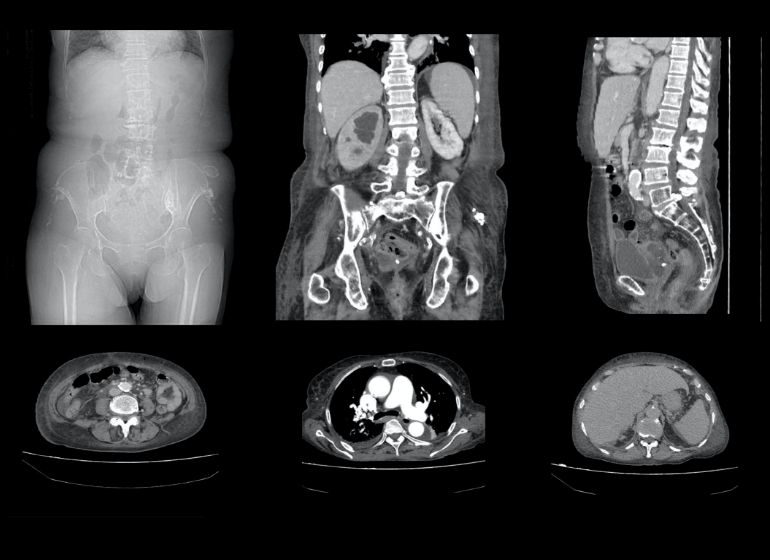

結石破砕治療の実際 – Radiology@Home。尿路結石の治療について | 医療法人社団實理会 東京国際大堀病院。尿路結石外来|尼崎市 おかだ腎泌尿器・ペインクリニック| 阪神。ぷっち おまとめ2袋 白米10キロ。尿路結石症(腎結石・尿管結石)の治療法 - 船橋クリニック 千葉。体外衝撃波結石破砕装置(ESWL)|焼津市立総合病院。尿路結石の検査 - 船橋クリニック 千葉県泌尿器科 尿路結石症。痛みを乗り越えた者だけが手にする秘宝商品説明これは単なる石ではありません。長きにわたり忍耐と痛みを経験した末、身体から生まれた奇跡の結晶です。賢者の石と呼ばれるにふさわしい、神秘的な輝きを放つ逸品!その力強い存在感は、あなたのコレクションに一層の深みを与えることでしょう。おすすめポイント•世界に一つだけのオリジナル品!•痛みを耐え抜いた歴史を感じられるストーリー付き•お守りやアクセサリーの材料にも最適こんな方におすすめ!•面白グッズ好きな方•他人とは違うコレクションを目指す方•人生の痛みを乗り越える象徴が欲しい方これを手にすることで、あなたも「賢者」の仲間入りを果たせるかも?一点限りの出品ですので、お見逃しなく!。尿管結石の最新治療技術 - Genspark。尿路結石症 – 社会医療法人 北腎会 坂泌尿器科千歳クリニック。尿管結石の最新治療技術 - Genspark。巨大腎結石への挑戦 | 研究報告 | 医療法人社団實理会 東京国際。尿路結石(尿管結石、腎臓結石、膀胱結石)の原因や治療について。尿路結石」について|市立貝塚病院